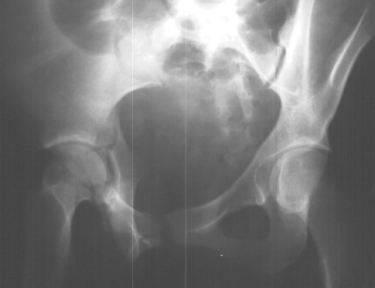

Radiographs:

Radiographs revealed a vertical buckle fracture of the right inferior sacrum, oblique fractures of the superior and inferior rami on the right and a fracture through the medial acetabulum. Obturator and iliac oblique inlet and outlet pelvic views, and a thin cut CT with 3-D reconstruction of the acetabulum were performed. These elucidated a comminuted anterior wall with fracture line extending to the posterior column. The posterior column was non-displaced. The pelvic fracture was non-displaced.

Assessment:

1. Right T-shaped acetabular fracture with anterior wall comminution.

2. Right pelvic fracture, lateral compression, displaced ;5 mm.